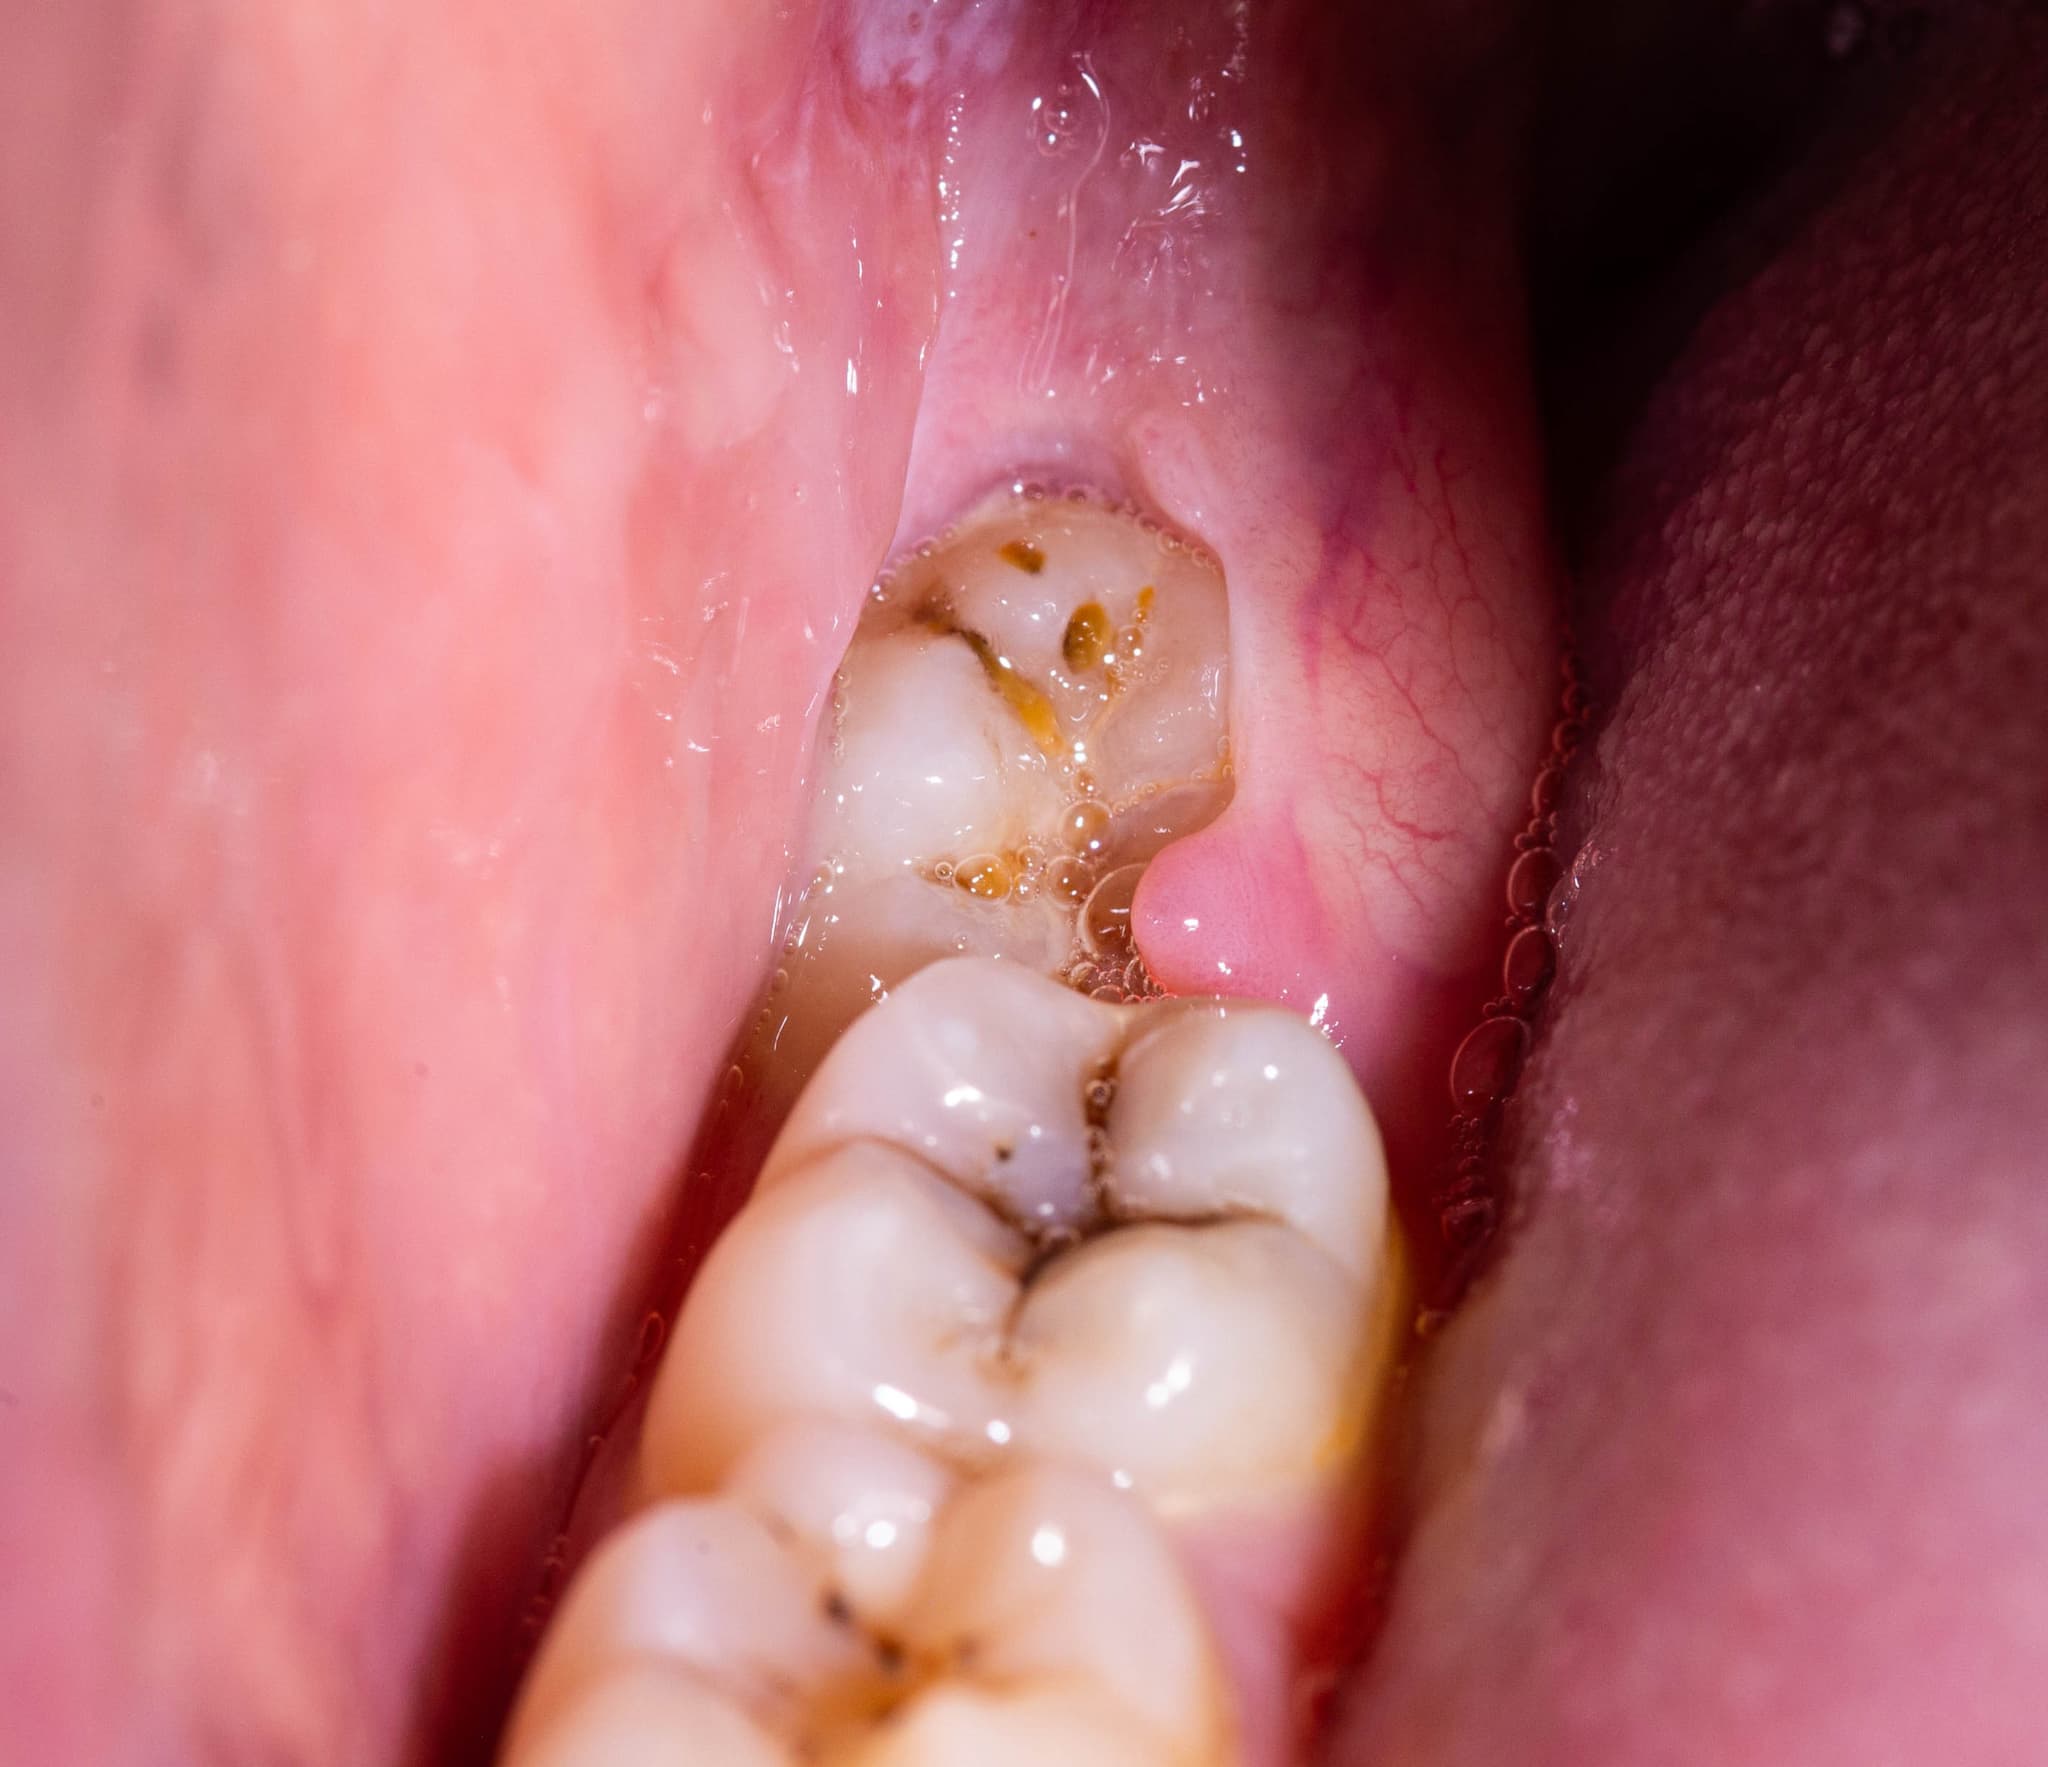

智歯周囲炎は、親知らずの周囲に炎症が起こることで発生するトラブルです。

親知らずが部分的に歯ぐきから顔を出している状態、いわゆる半埋伏(はんまいふく)の状態でよく見られます。このような状態では、親知らずと歯ぐきの間に隙間が生じ、そこに細菌が入り込みやすくなります。

炎症が進行すると、腫れや痛みに加えて、口が開きにくくなる開口障害や、顎の下のリンパ節が腫れて痛むこともあります。重症化すると発熱を伴うこともあり、放置すると日常生活に大きな支障をきたす恐れがあります。

智歯周囲炎は慢性化しやすく、いったん痛みが引いても再発するケースが多いため、根本的な治療として親知らずの抜歯を勧められることも少なくありません。

虫歯

親知らずは、位置が奥まっているため歯ブラシが届きにくく、プラークが溜まりやすい環境にあります。その結果、虫歯になりやすく、進行すると痛みを引き起こすことがあるのです。

特に隣の歯と密接して生えている場合、親知らずと第二大臼歯の間に食べかすが挟まりやすくなり、虫歯になるリスクが高まります。虫歯が進行すると、知覚過敏や鋭い痛みを感じるようになり、やがては神経に達することでズキズキとした強い痛みを伴うことになります。